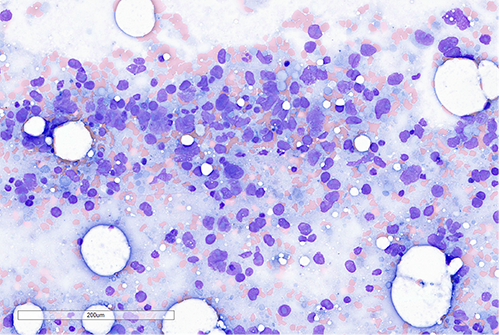

Bone marrow aspirate smear was hypocellular and paucispiculate. In areas with preserved cellularity, large atypical cells with giant pleomorphic nuclei and prominent macronucleoli are identified.

A higher power view of the atypical cells.